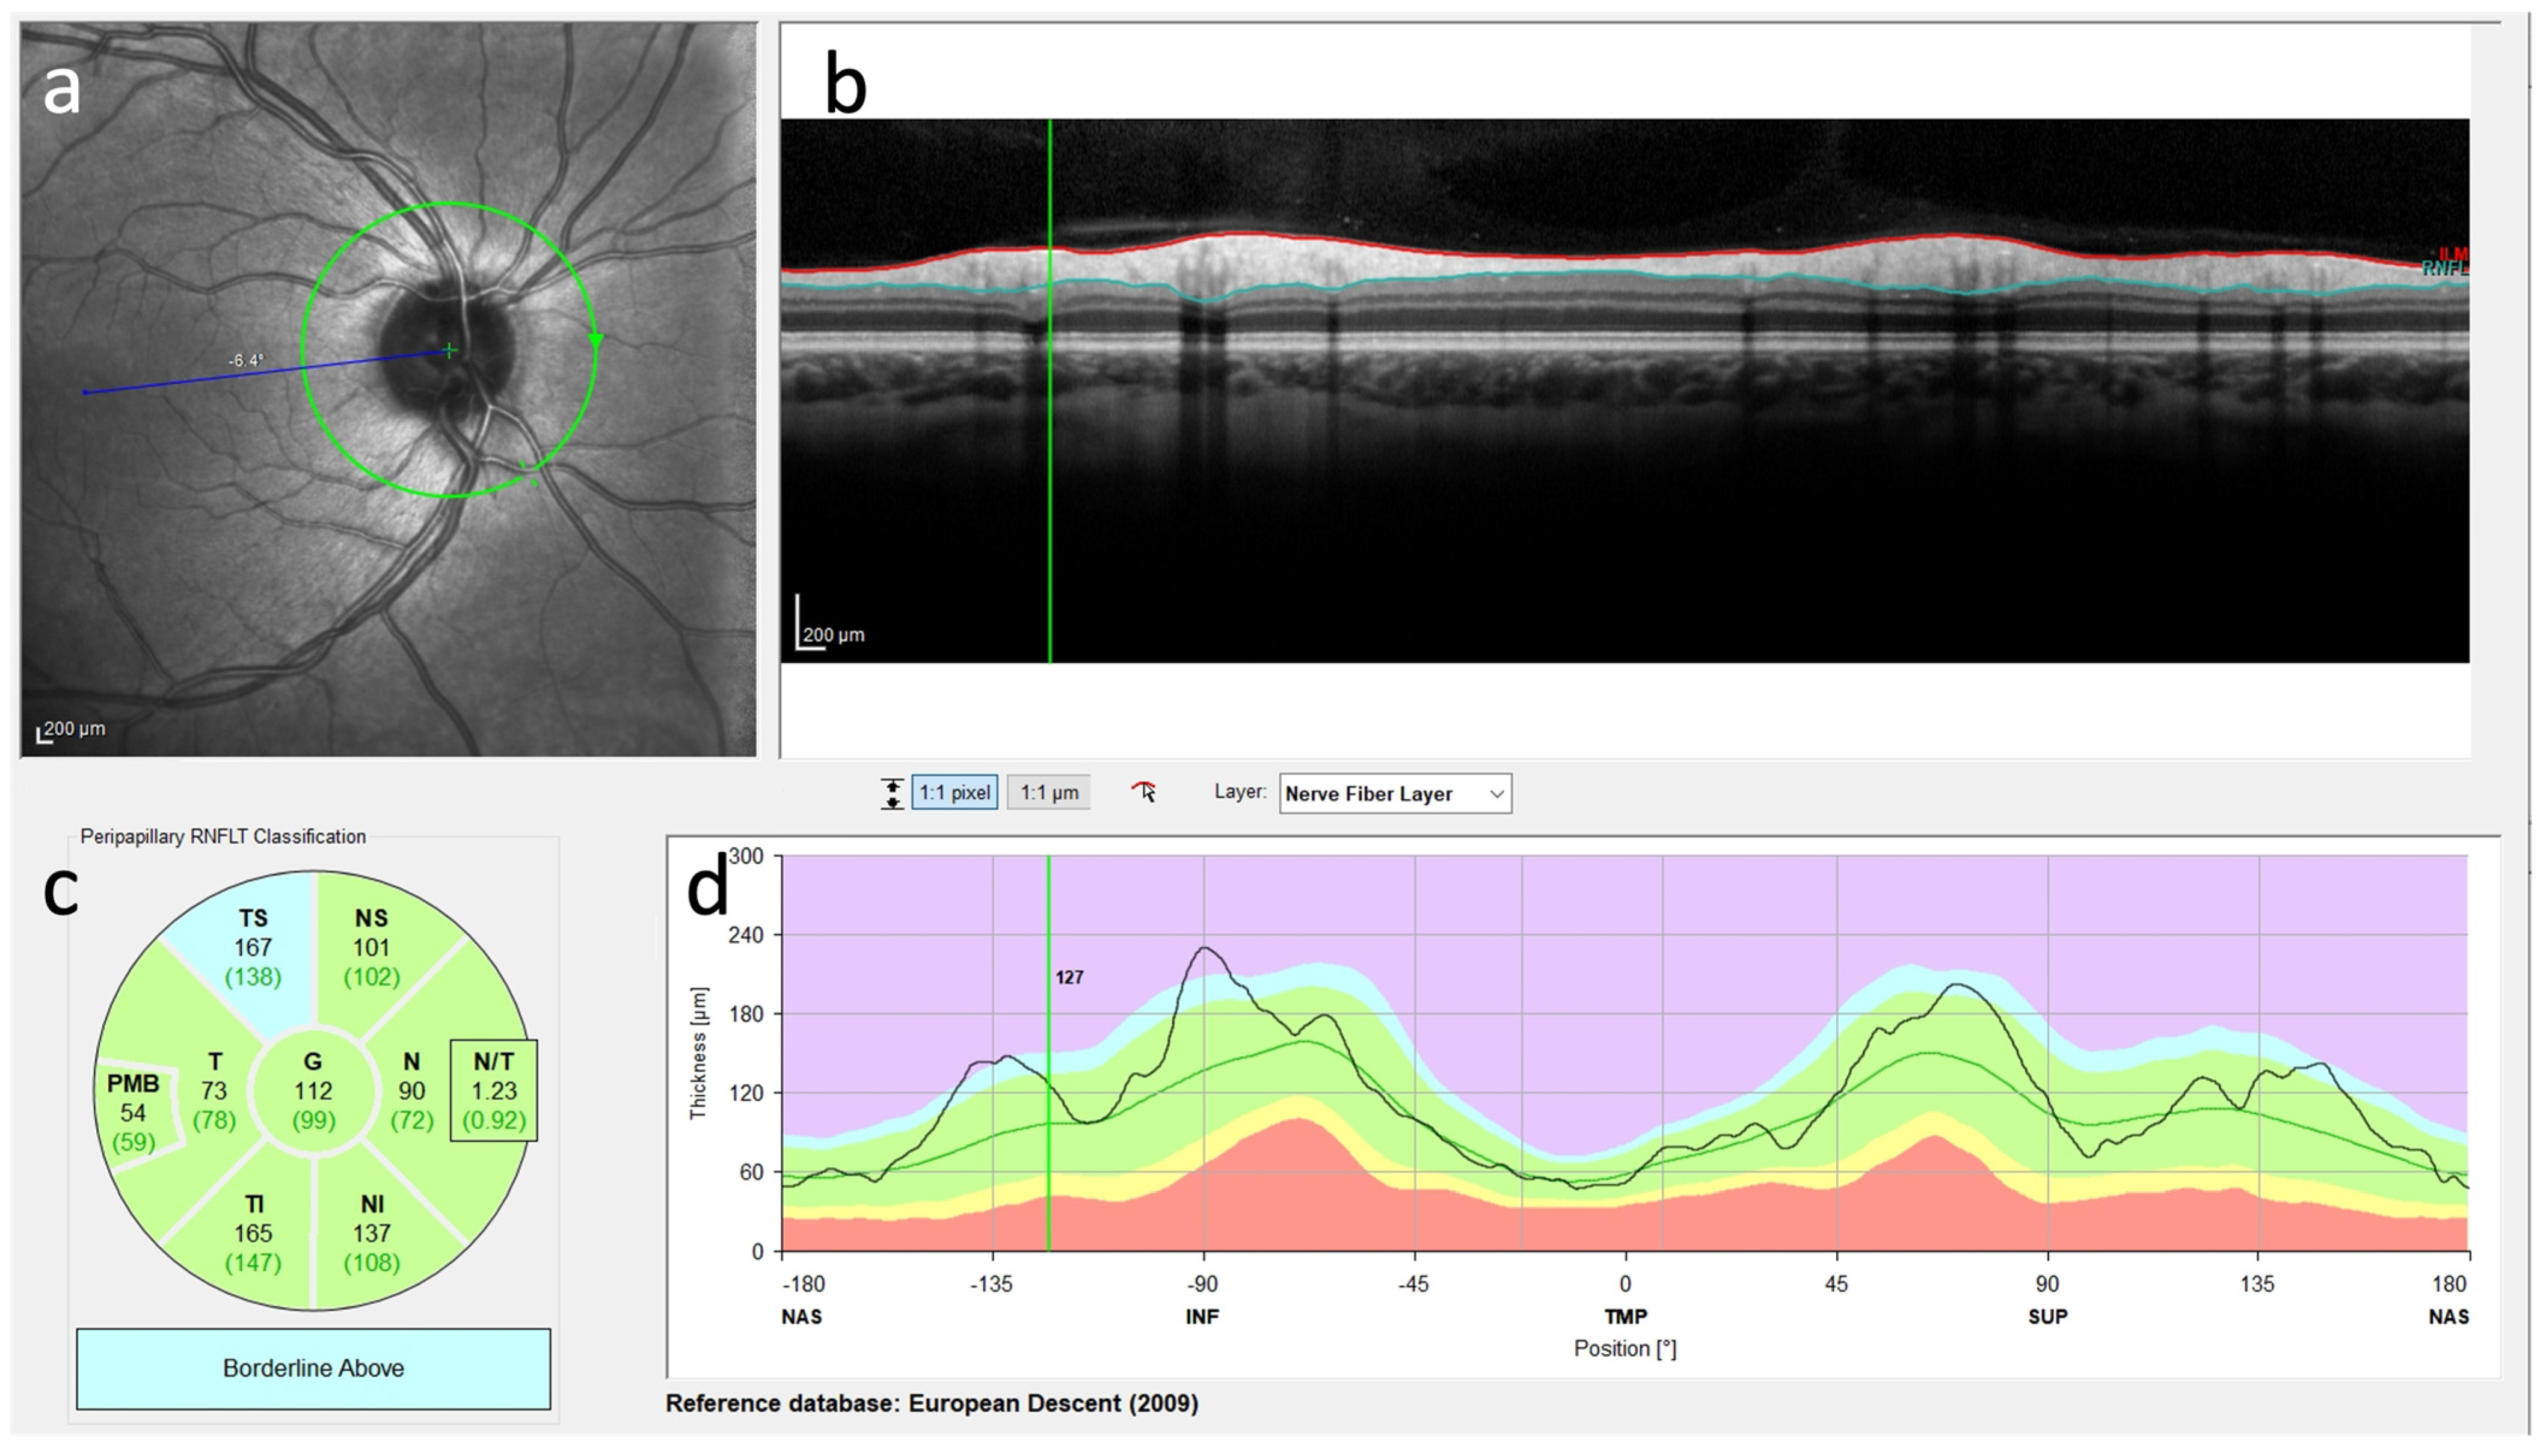

2.3. Optical Coherence Tomography and Retinal Nerve Fiber Measurement

3.4. OCT in Leukodystrophies